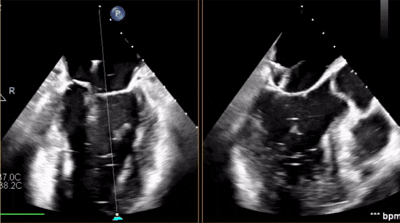

術(shù)中剪影

術(shù)中操作

全麻后,在心前區(qū)的肋間切開(kāi)3-4CM小切口,暴露心臟的心間位置,將二尖瓣夾合系統(tǒng)送入左心房,順利到達(dá)病變二尖瓣區(qū)域。在經(jīng)食道超聲輔助下,術(shù)者通過(guò)反復(fù)評(píng)估二尖瓣反流位置、抓捕位置、反流程度,最終在3區(qū)位置垂直于二尖瓣閉合線方向進(jìn)行巧妙?yuàn)A合最終植入1枚ValveClamp®MVC-Ⅱf夾。手術(shù)中導(dǎo)管操作時(shí)間僅30min,共夾合2次。患者術(shù)后反流程度從大量轉(zhuǎn)至微量,手術(shù)取得圓滿成功。